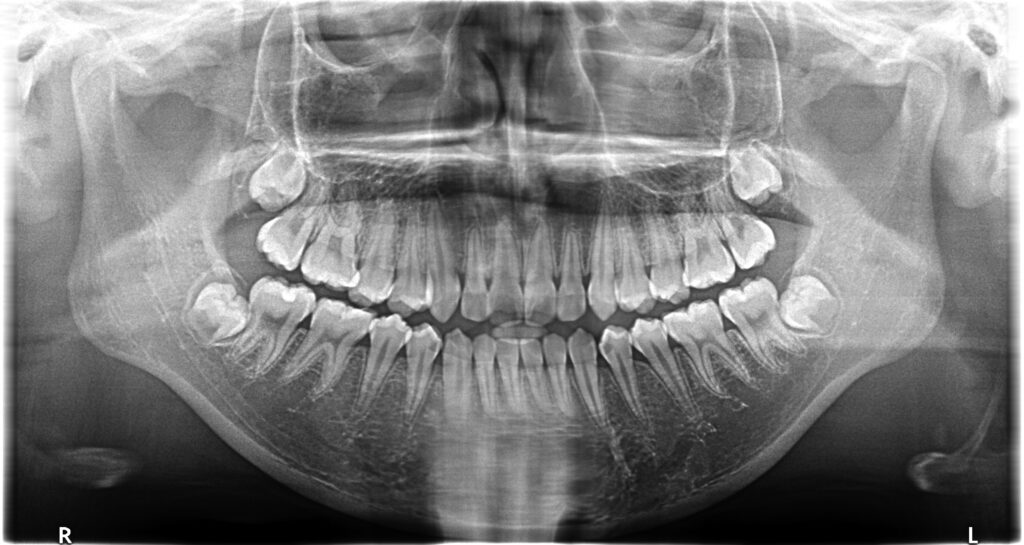

治療前

• 初診:2012年、9歳女児、

• 主訴:出っ歯と歯のがたがたが気になる。

• 診断:1級過蓋咬合、上下前歯叢生、上顎左右側切歯クロスバイト

• 治療方針:非抜歯で行う。虫歯予防(フッ素)、歯磨き指導、上下拡大床→最小限のデイスキング→マウスピース矯正→下親知らずの抜歯、保定→メンテナンス